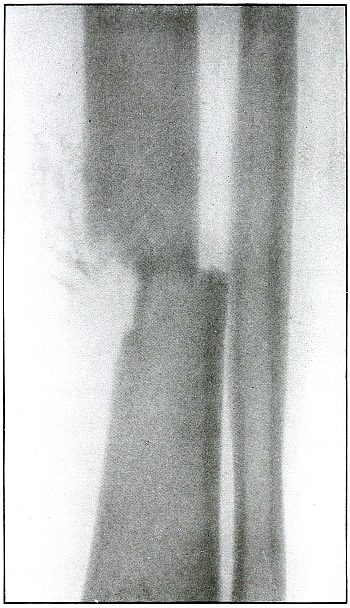

Plate 51.

[Pg 113]

Rifle—Plate 51.

LOWER EXTREMITY.

Gunshot Wound of the Thigh,

with Lodgment of the Missile.

As there is no injury to the bone, the bullet is not deformed. Its

penetrating power was not great enough to carry it through the tissue

so it must have struck the leg at extreme range when its energy was

almost spent.

The actual length of the bullet is 1.25 inches; the length of the

shadow is about 1.50 inches.

The increased length and the relatively slight density of the shadow

indicate the bullet to be some distance from the plate. The case

history places the wound in the right thigh, and the posterior surface

of the leg lay next to the photographic plate. As the density of the

shadow is not greater than the thickest portion of the bone, the

bullet probably lies in front of the border of the outer tuberosity of

the femur.

Although the surgeon’s diagnosis had to be made from the only

available plate, there is something of a speculative element in these

deductions, because if the reaction in the knee joint prevented the

patient from extending the leg the increased length of the bullet

shadow could be accounted for by this position, which would permit the

bullet to lie behind the bone and yet far enough from the plate to

account for the shadow enlargement. The nose of the bullet is at

the epiphyseal line, which is shown in the femur.